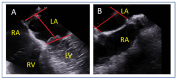

Mitral regurgitation (MR) is a common valvular heart disease associated with significant morbidity and mortality. For patients at high or prohibitive surgical risk, mitral transcatheter edge-to-edge repair (M-TEER) offers a less invasive alternative to surgery. This review outlines key aspects of patient selection and procedural planning for M-TEER, with a focus on clinical and echocardiographic criteria essential for success. Comprehensive imaging-especially 2D and 3D transesophageal echocardiography-is critical to assess leaflet anatomy, coaptation geometry, and mitral valve area. Selection criteria differ between primary and secondary MR and are guided by trials such as COAPT and MITRA-FR. Optimal outcomes rely on careful screening, anatomical suitability, and multidisciplinary evaluation. With growing experience and advancing technology, M-TEER has become a transformative option for treating severe MR in non-surgical candidates.